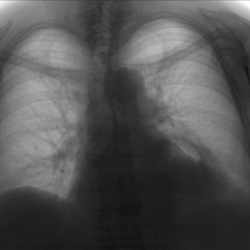

Женщина 70 лет. Архива нет. В левом легочном поле, тень имеющая двойной контур, ГПОД?